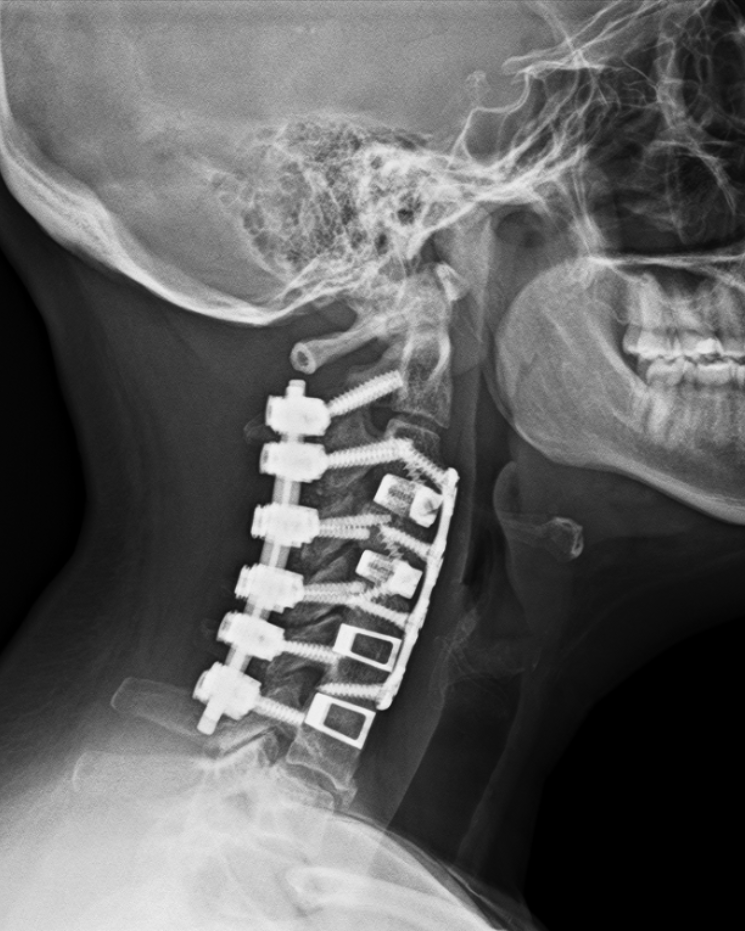

So imagine my surprise when a few months shy of my 10 year anniversary (traditionally tin or aluminum, but I think titanium is more appropriate), I had a “minor event”, and the follow-up appointment revealed I needed a second surgery, which would be more complicated than the first and the only available day for the rest of the year was my birthday.

- I think my x-rays are really cool and wanted to share them!

I hope you’ve enjoyed this little tour of my spine (cross your fingers this is the last intervention!) and as always, if I can be of service to you, please do not hesitate to reach out to schedule a Complimentary Design Discovery Consultation.